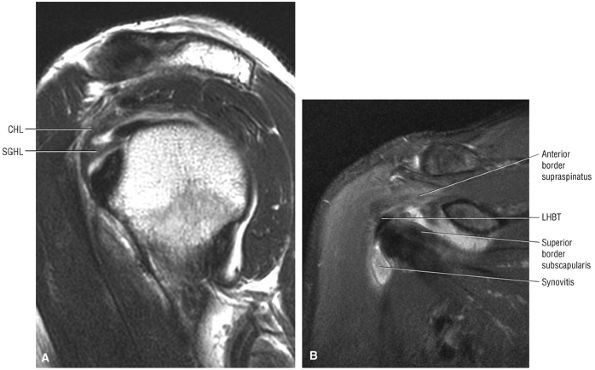

FIGURE 8.94 ● (A) The biceps pulley complex is sectioned in the sagittal plane at the level of the proximal, middle, and distal rotator cuff interval. The confluence of the CHL and SGHL occurs at the middle and distal aspects of the rotator interval. A T-shaped junction is formed between the SGHL and CHL at the mid-interval, superior to the humeral head. An anterior U-shaped sling is shown at the distal interval at the entrance to the bicipital groove. (B) An anterior coronal FS PD FSE image demonstrates the biceps tendon contained between the CHL and SGHL components of the biceps pulley.

|

FIGURE 8.95 ● Sagittal MR arthrograms. (A) The anterior biceps sling is formed by the confluence of the CHL and SGHL anterior to the LHBT. (B, C) The T-shaped junction of the SGHL and CHL at the midportion of the rotator cuff interval.